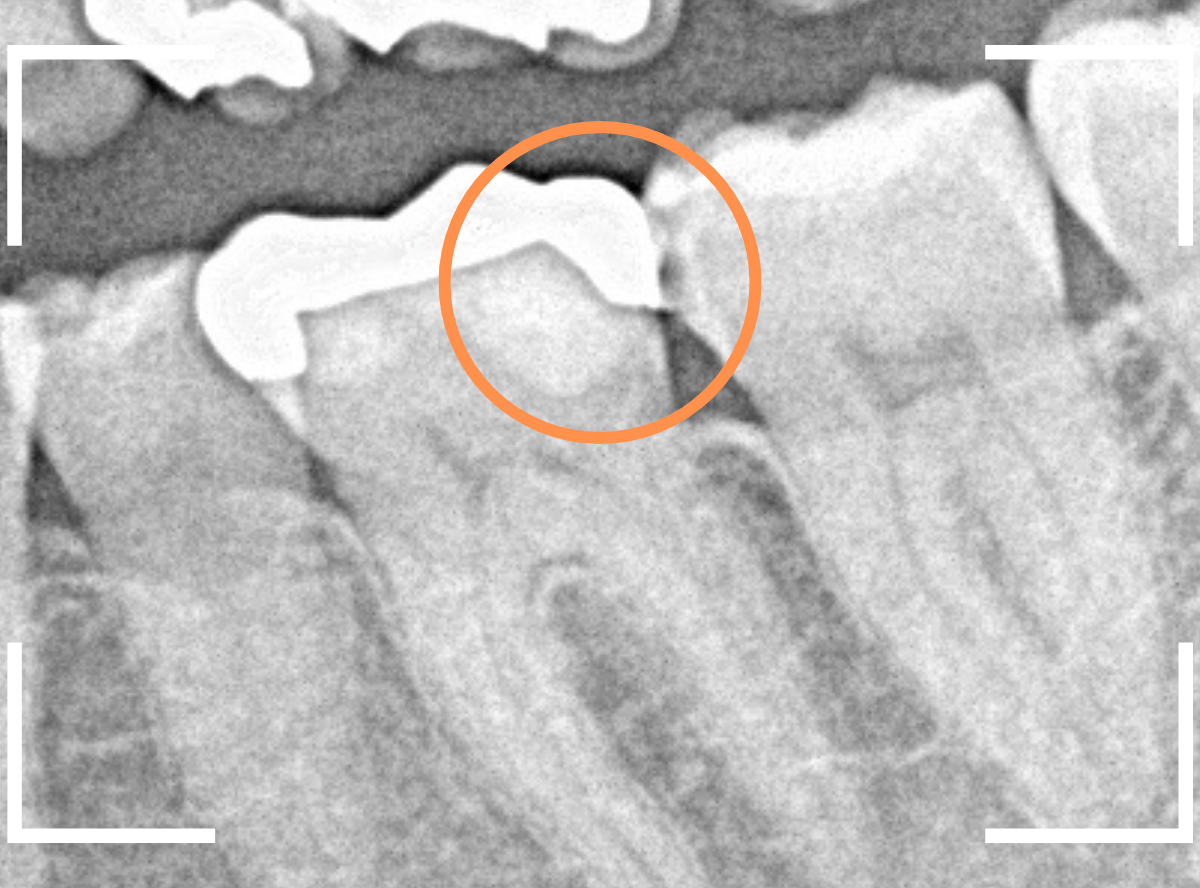

レントゲン写真で確認します。

金属のつめものの下が、神経まで達する大きな虫歯になっています。